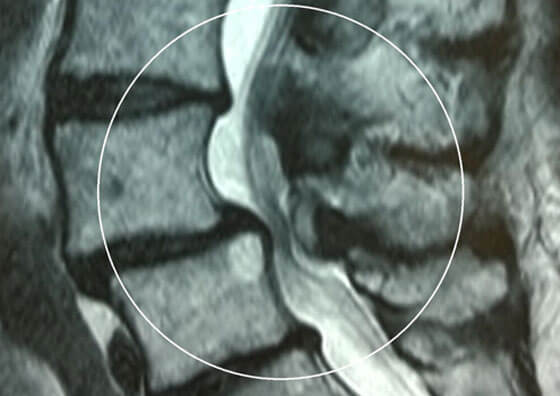

This is used to treat symptoms of spinal claudication or sciatica due to narrowing of the lumbar spinal canal causing nerve compression. The procedure entails a full anaesthetic, a small incision and a few days in hospital.

The first step of surgery is to use a mobile X-ray machine to find the correct spinal level and then make a short incision in the back. Magnifying operating loupes are used to give a clear view of the involved nerves and gently remove the bone and thickened ligaments that are compressing them. Care is taken to make sure that there is no ongoing bleeding and the wound is sutured.